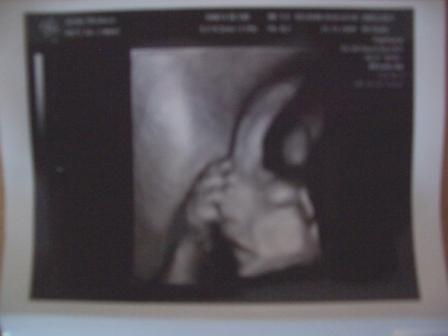

HI, hatte gestern VU, mit dem Mumu ist alles in Ordnung, sonst die Werte auch, Eisen ist nur etwas niedrig. Mit unserem kleinen ist auch alles super wiegt jetzt 650gr. Dann hat sie mich noch überrascht und ein 3D Bild gemacht, er lag gerade so günstig und nächste Woche mache ich ja eh 3D...oh ist das schön... Mir geht es so nicht so gut, ich hab Husten und Schnupfen und gestern Abend auch noch Fieber bekommen...hoffendlich ist es bald rum...ich kann nicht mehr, meine beiden Mädels sind auch zu hause mit Husten, gestern hatte die kleine Fieber und heute hat die große...oh Hilfe und mein Mann ist auch krank, er ist vormittags für 4 Stunden in der Firma und kommt dann zum Mittag nach hause. So genug gejammert, jetzt kommt das süsse Bildchen... LG Bea

Bild zu VU gestern mit 3D Bildchen - Forum für März - Mamis